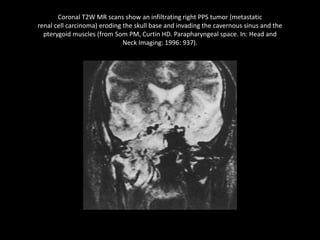

Coronal T2W MR scans show an infiltrating right PPS tumor (metastatic

renal cell carcinoma) eroding the skull base and invading the cavernous sinus and the

pterygoid muscles (from Som PM, Curtin HD. Parapharyngeal space. In: Head and

Neck Imaging: 1996: 937).

Coronal T2W MRscans show an infiltrating right PPS tumor (metastatic renal cell carcinoma) eroding the skull base and invading the cavernous sinus and the pterygoid muscles (from Som PM, Curtin HD. Parapharyngeal space. In: Head and Neck Imaging: 1996: 937).